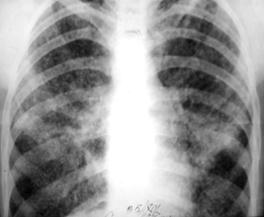

Рис.2. Инфильтрат. Просветление обозначает наличие деструкции (стрелка). Вокруг – множество очагов бронхогенного отсева